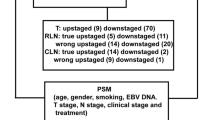

NTR and prognosis in high-risk group

We further analyzed the high-risk group patients. ROC curve analysis revealed that the optimal cutoff value of the NTR for predicting DMFS was 0.23 in the LH group, 2.35 in the HL group, and 1.29 in the HH group. The high-risk group patients were again reorganized into a low NTR group (NTR ≤ 0.23, ≤ 2.35, and ≤ 1.29 in the LH, HL, and HH groups, respectively) and a high NTR group (NTR > 0.23, > 2.35, and > 1.29 in the LH, HL, and HH groups, respectively).

Multivariate analysis with other known prognostic factors, including tumor stage (T stage), nodal stage (N stage), and age, revealed that the NTR was an independent prognostic factor for DMFS (HR = 2.037, 95% CI: 1.039–3.992, P = 0.038), PFS (HR = 1.636, 95% CI: 1.021–2.621, P = 0.041), and OS (HR = 2.543, 95% CI: 1.214–5.325, P = 0.013). The results of the multivariate analysis are summarized in Table 2.